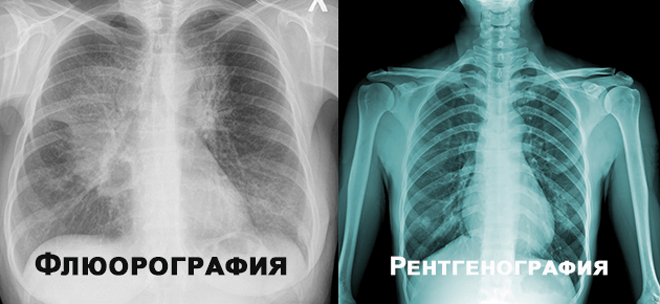

Чим відрізняється рентген від флюорографії? Це очевидно, а водночас — ні. «Рентген» та «флюорографія» звучать як заплутані медичні терміни.